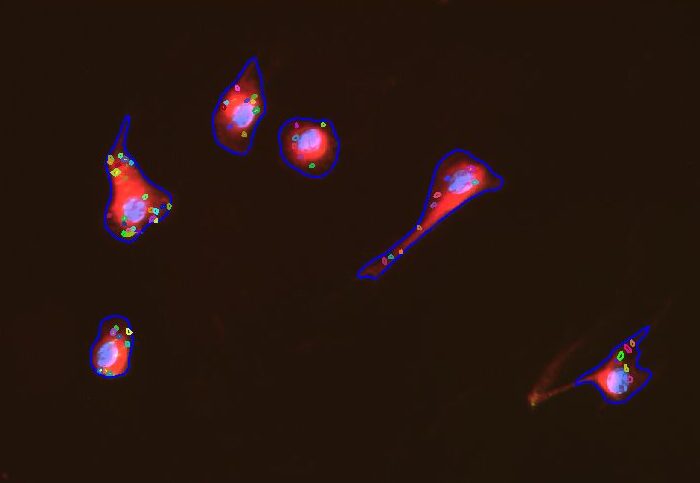

- Biomedical

- Cell Biology

- Life Science